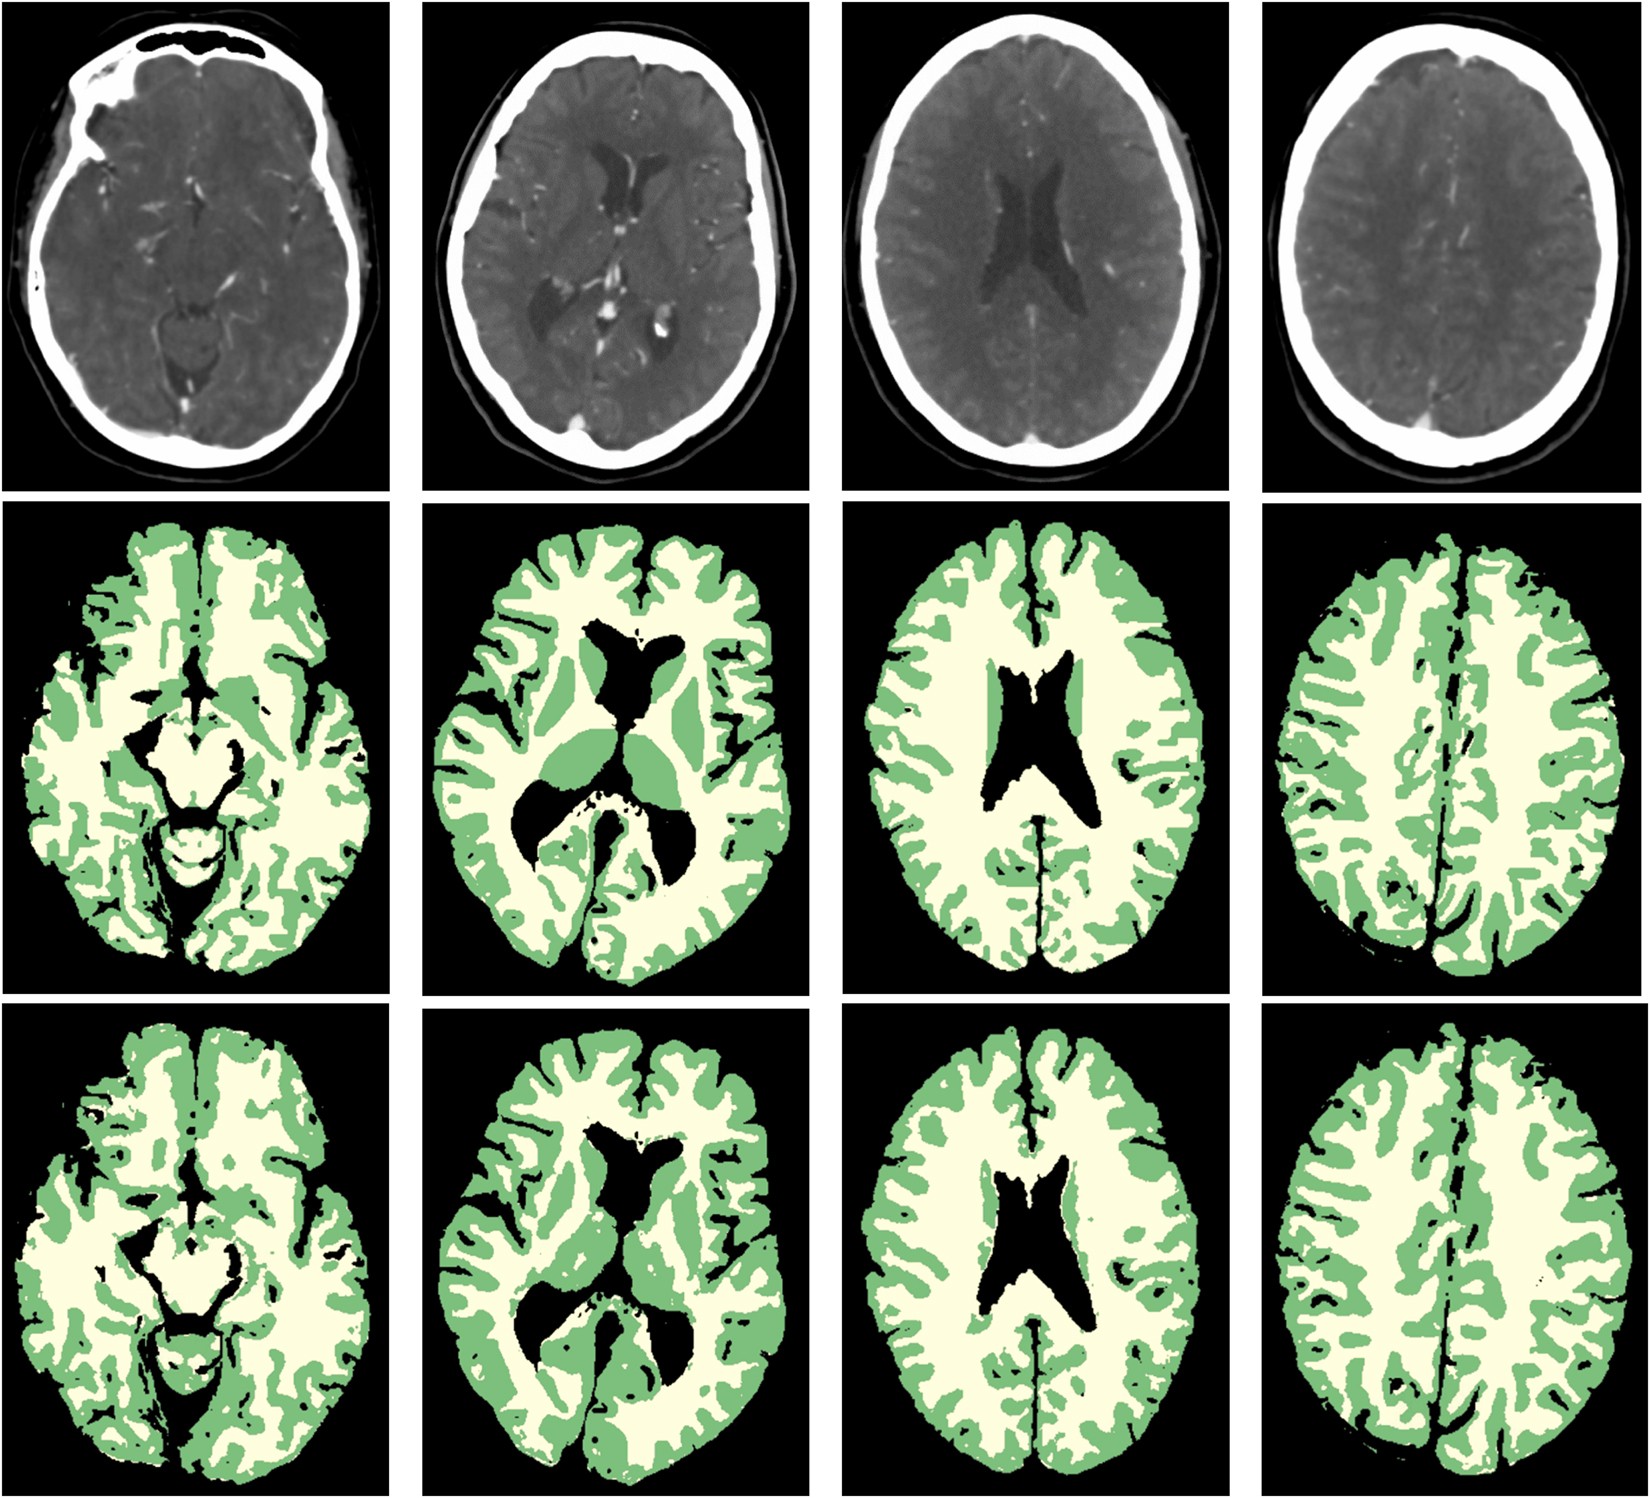

Figure 2

From: White Matter and Gray Matter Segmentation in 4D Computed Tomography

WM and GM segmentations of four different patients. From left to right: axial slices at approximately the level of the Circle of Willis, basal ganglia, lateral ventricles and centrum semiovale. From top to bottom: weighted temporal average (window width/level 300/100 HU); the reference standard; the final WM (yellow) and GM (green) segmentation with the proposed method.